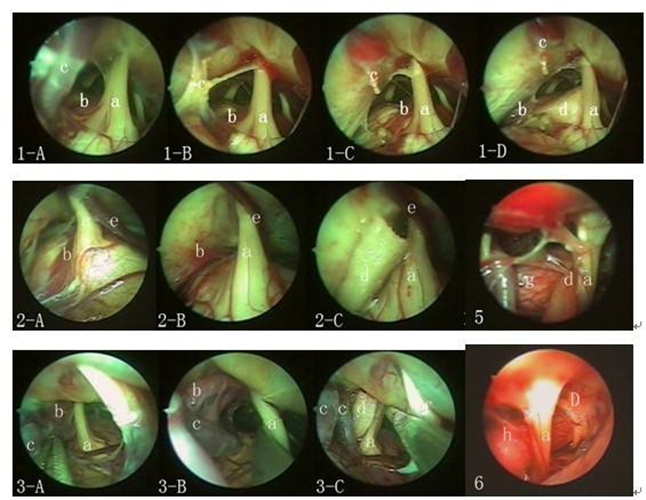

小腦腦梗塞組圖

小腦腦梗塞手術

小腦腦梗塞